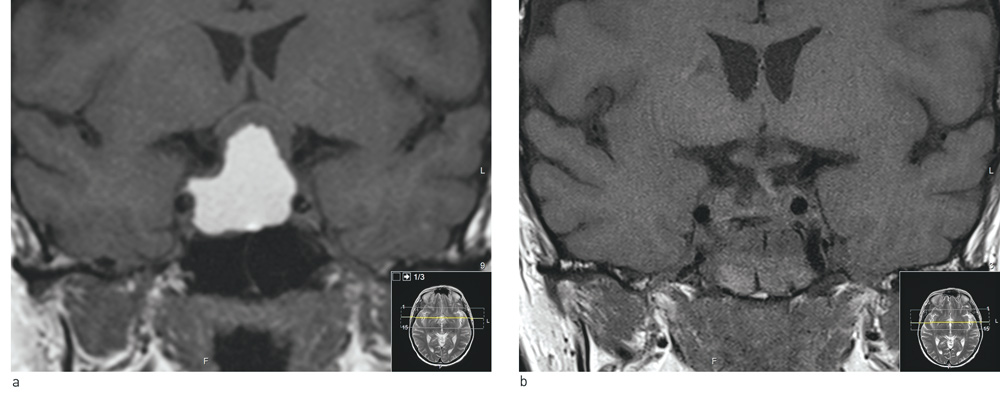

An MRI scan of the pituitary gland immediately postoperatively (Fig. 1B) showed no sign of residual tumour, and the optic paths were free. The histology results revealed that the tumour was a non-hormone-producing pituitary adenoma with a low level of the proliferation marker ki67.

Figure 1  Coronary T1-weighted MRI images without contrast. a) Large opacity in sella turcica that extends up in the…

Figure 1 Coronary T1-weighted MRI images without contrast. a) Large opacity in sella turcica that extends up in the suprasella direction. The optic nerves and optic nerve decussations have been pushed upwards and are seen as a thin, half-moon shaped strip above the tumour. The tumour has a solid component with a low signal just under the optic paths. The large cystic component is seen with a high signal and parallels the internal carotid artery bilaterally. b) Post-operative status. Tumour was removed transphenoidally. There are copious blood products in the sphenoidal sinus. The optic nerves and optic nerve decussations are now lying free and their thickness has normalised. Under them the pituitary stalk is seen in the mid-line with a slight deviation to the left (right in the picture)